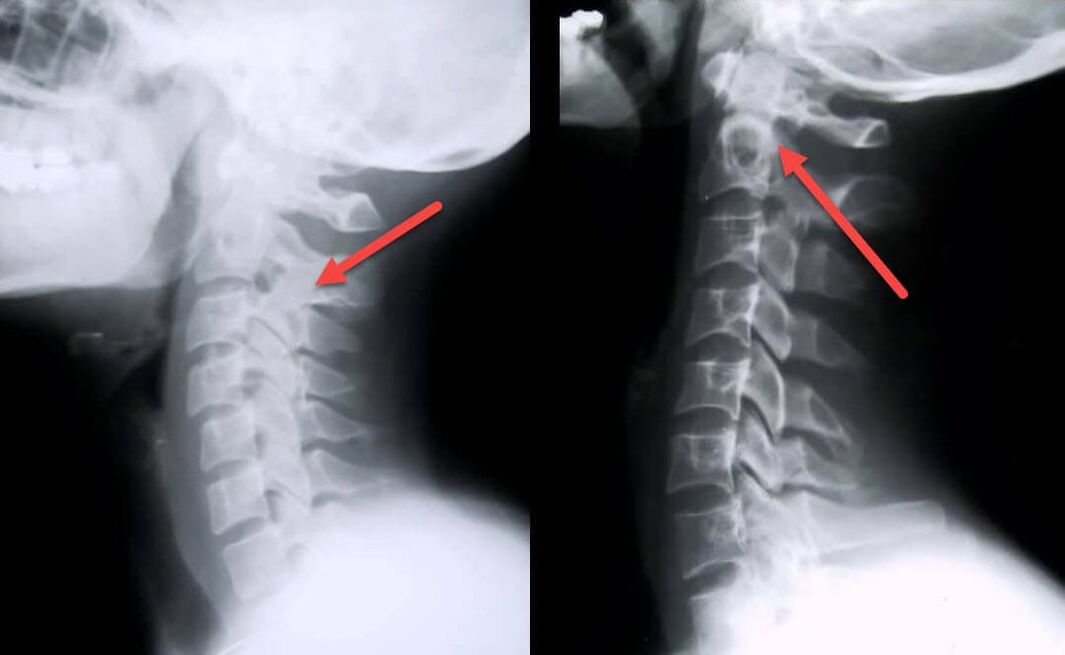

The most informative diagnostic procedure is x-ray.1st degree pathologies correspond to the 1st or 2nd radiological stage.The resulting images show typical signs of the disease.

| Radiological stages of first degree cervical osteochondrosis. | Characteristic signs |

|---|---|

| Stage 1 | Minor changes in the curvature of the spine in the cervical region, affecting one or more segments. |

| Stage 2 | Slight thickening of the intervertebral discs, deformation of the uncinate processes, straightening of the lordosis, minor growths of bone structures. |